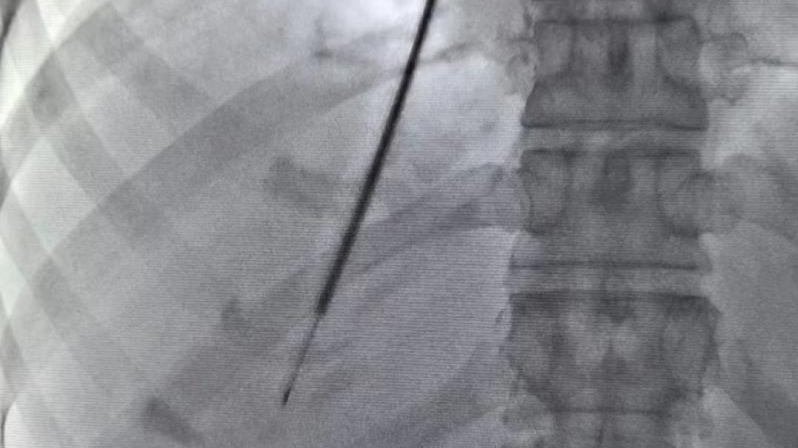

【新医技术谈】经颈静脉肝内活检术—疑难危重肝病诊断新选择

近日,新疆医科大学第一附属医院感染病·肝病中心三科联合介入放射科,首次在疆内成功开展“经颈静脉肝内活检术(TJLB)”技术。该技术通过微创的方法为不明原因的疑难危重肝病患者进行肝组织活检,通过获得满意的肝组织标本为患者提供明确诊断,及时给予患者更加有针对性的诊疗方案,帮助患者转危为安。经颈静脉肝内活检术(X光下)当前,肝脏病理检查是临床中用以诊断疑难、复杂肝病的主要手段,而最常用的获得肝组织标本的....查看详情 >